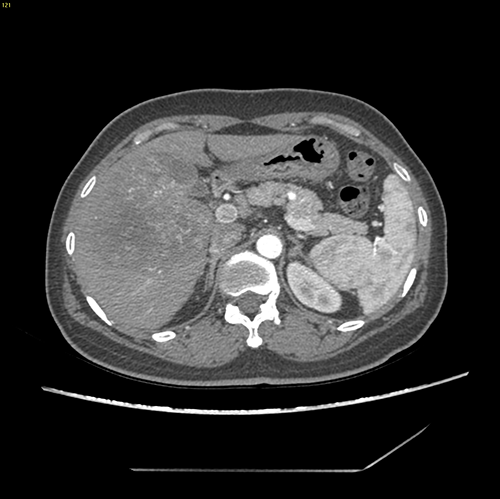

右肝癌----S567切除